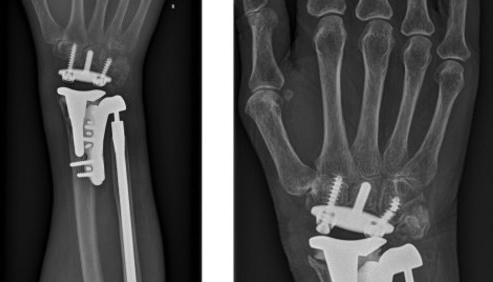

- Presentamos una técnica para fijar la prótesis de la articulación del radiocubital distal semi-restringida, así como una prótesis total de muñeca mediante una prótesis de brida impresa tridimensional personalizada en el borde cubital del radio.

- Tres años después de la cirugía, el paciente permaneció sin dolor, con flexión de 60 °, extensión de 75 °, pronación de 80 ° y supinación de 80 °.